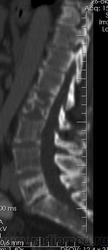

Костное окно:

По имеющимся файлам-дайком я не нашла признаков опухоли. Имеется множественное остеолитическое поражение позвоночника, ребер, грудины, частично - таза. Лимфоузлы не увеличены. Тоже поставила бы на первое место миеломную болезнь. Диагностирование её не всегда простое дело. Поражена грудина и, наверное, нужно посоветоваться с онкологом (гематологом) стоит ли сделать стернальную пункцию.Советую написать в личку tatyana.